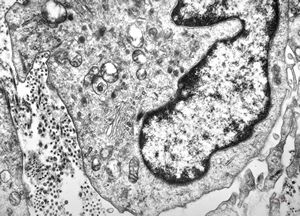

M, 43y. | myeloid leukemia

M, 43y. | myeloid leukemia … Auer bodies